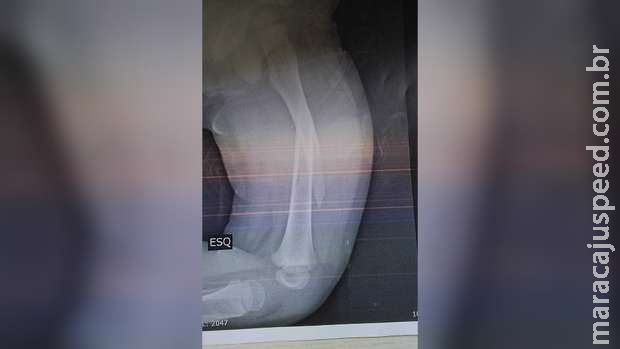

No dia do ocorrido, a mãe foi com o filho na UPA (Unidade de Pronto Atendimento) Coronel Antonino, fez o raio-x, que constatou a lesão.

Com a gravidade do machucado, a criança foi transferida para Santa Casa, onde o médico informou que teria que fazer a cirurgia ou engessar da cintura para baixo, opção escolhida pela mãe.

Segundo a nota, o menino não chegou a cair, porém, com o escorregão, uma perna foi para frente e a outra para trás (a perna esquerda).

“Além disso, a perna esquerda foi totalmente imobilizada da cintura para baixo e parte da perna direita, para evitar que a criança se mexa e garantir a recuperação total”, complementou.